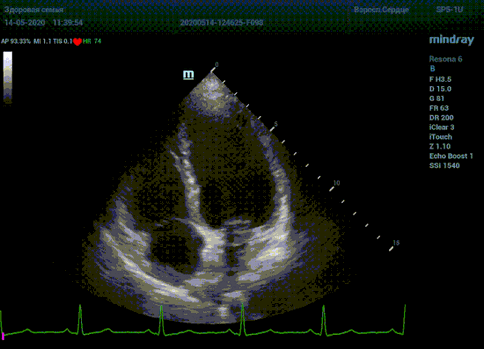

Что могут предложить современные приборы? Приборы нашего времени являются мощными вычислительными машинами, способными обрабатывать полученную информацию даже без помощи человека. Система автоматического вычисления фракции выброса – AUTO EF на приборах серии Resona компании Mindray сделает все за вас. За пару секунд прибор сам отыщет нужную фазу сердечного цикла и произведёт измерение и расчеты, а также покажет график изменения объема в сердечном цикле. От Вас требуется только получить качественное 4С и 2С сечение. Впрочем, прибор всегда оставляет возможность коррекции, если доктор имеет свое мнение на расположение точек планиметрии или момента измерения по ЭКГ каналу.